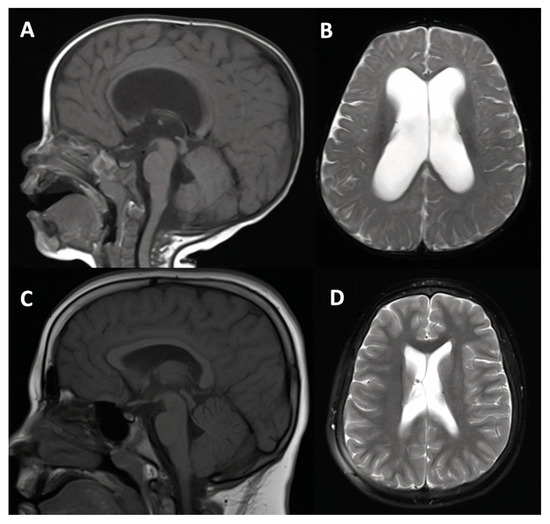

3.1.3. Case #4. Congenital Hydrocephalus with Prematurity

| 4 | 18 m, F |

|